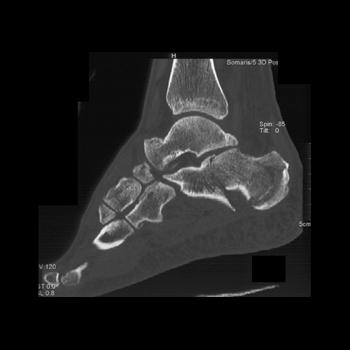

Foot Pathology: Calcaneal fractures

The calcaneus is the most commonly fractured tarsal bone. Calcaneal fractures are classified as intraarticular and extraarticular. The intraarticular fracturesaccount for 70-75% of calcaneal fractures and carry a worse prognosis. The inciting trauma is usually a fall or motor vehicle accident, and these fractures are bilateral in 10% of cases. Concomitant ipsilateral lower extremity fractures are present in 20-46% of cases, and spinal fractures in 10-30%. Extrarticular fractures (Figure: extraarticular fracture of calcaneus) account for 25-30% of calcaneal fractures, and are the sequela of a twisting injury. Anatomic regions affected include the anterior or medial process, the sustentaculum tali, the body or the tuberosity. Severe fractures are readily evident on conventional radiographs; however, CT is essential for elucidating the extent of injury. The intraarticulur fractures are often comminuted and may be displaced. CT is also used for follow up after fracture treatment. CT is very helpful for detecting fracture malunion or nonunion . In addition, the presence and extent of secondary osteoarthritis is readily detected by CT. Several features of intraarticular fractures which can be elucidated on CT have been shown to correlate with the outcome. A central depression fracture has a worse prognosis than a tongue-type fractures, but a better prognosis than a comminuted fracture. An unsatisfactory result is more likely in the setting of subtalar incongruity, decreased fibulocalcaneal space and osteoarthrosis of the talonavicular joint and the ankle.